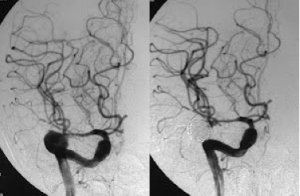

Στις παρακάτω εικόνες απεικονίζονται τα αποτελέσματα Εμβολισμού πραγματικών ανευρυσμάτων εγκεφάλου:

![]() |

Ανεύρισμα μέσης εγκεφαλικής αρτηρίας πριν και μετά τον εμβολισμό |